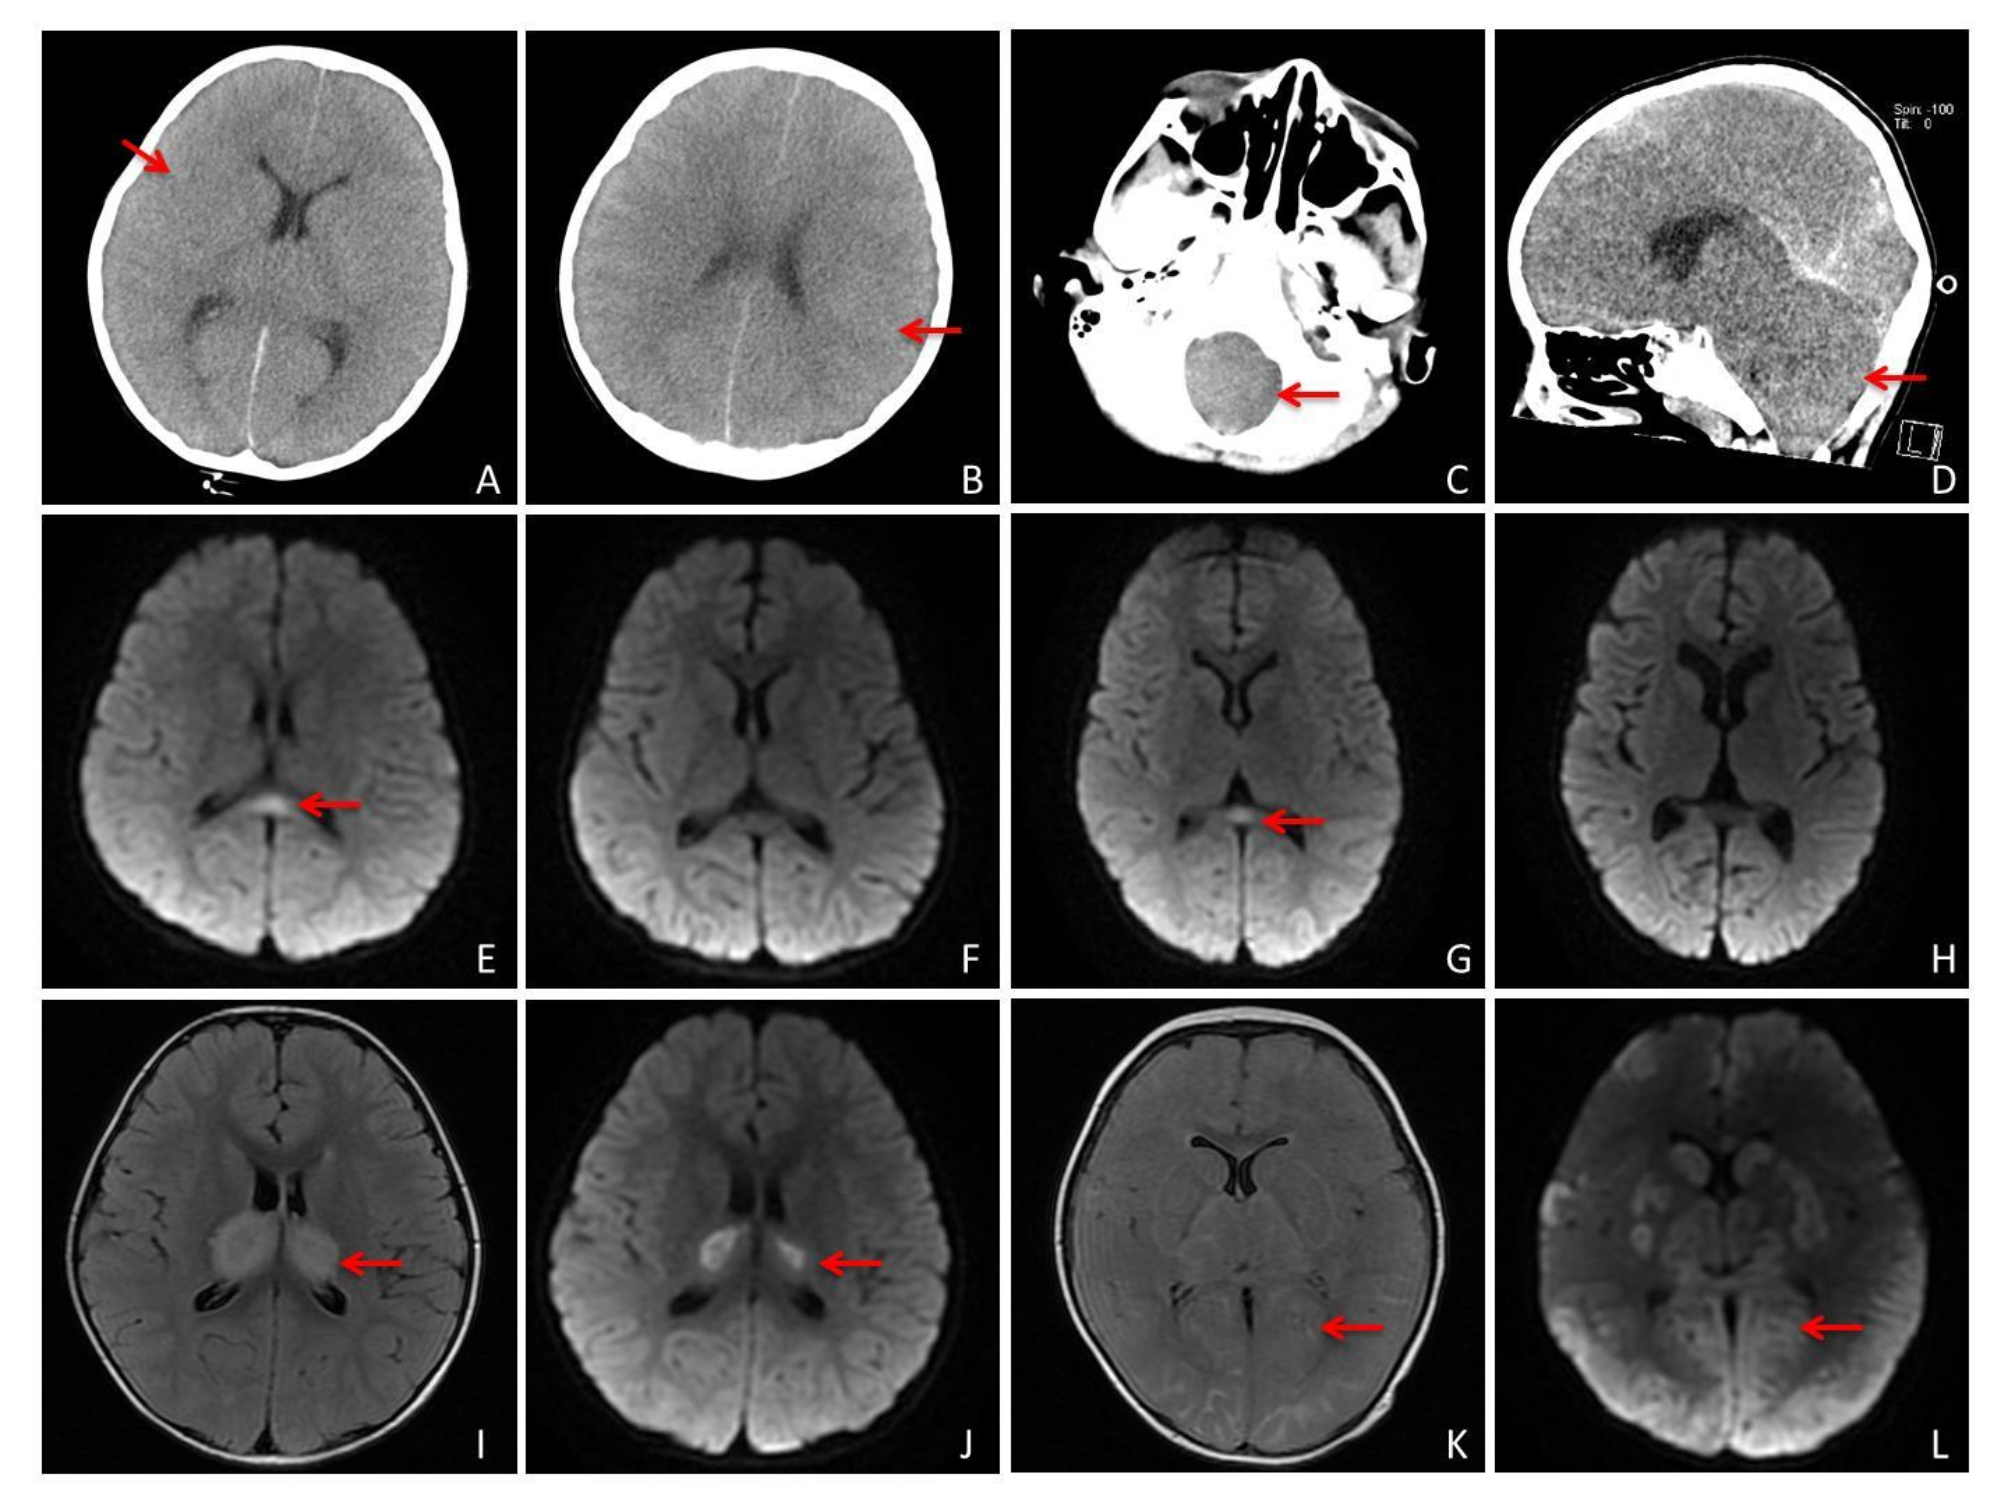

Fig. 2

Analysis of common cranial images of influenza-associated encephalopathy. Panels (A) and (B) Computed tomography of the brain showing diffuse brain swelling with poorly demarcated gray-white matter suggestive of acute cerebral swelling. Panels (C) and (D) Showing brain swelling with foramen magnum occipitalis hernia. Panels (E) through (H) Showing DWI sequences of magnetic resonance images (MRI) of mild encephalitis/encephalopathy with a reversible splenial lesion, where (E) and (G) are the initial images, and (F) and (H) are the follow-up images with lesion disappearance after 1 week. Panels (I) through (K) MRI showing acute necrotizing encephalopathy, with T2 Flair sequences in Figures (I) and (K), and DWI sequences in Figures (J) and (L), showing that the main lesion is located in the thalamic region.